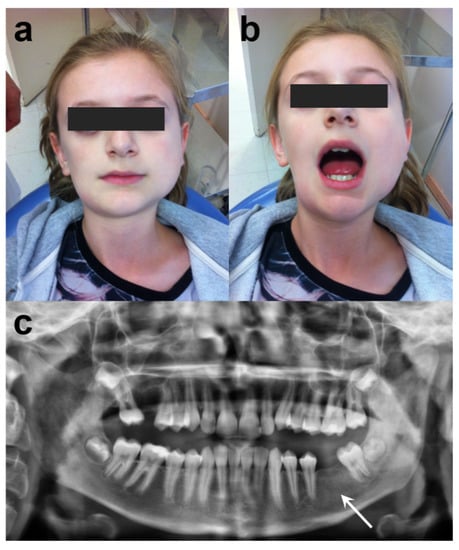

Clinical examination revealed facial asymmetry with the enlargement of the left mandible, and trismus (Figure 1). A firm and painful swelling in the right forehead and lower mandibular angle was detected by extraoral palpation. No fever, regional lymph nodes, arthritis or skin lesions had been reported. Intraoral examination revealed the loss of teeth #16 and #36. No carious lesions of the dentition were observed. There were no periodontitis or signs of infections in the mouth. Initial panoramic radiograph demonstrated diffuse radiopacities in the left mandibular ramus (Figure 1).

Figure 1. Initial presentation of patient: (a) frontal view of the patient, (b) limited mouth opening of 25 mm inter-incisor distance, (c) panoramic radiograph showing diffuse radiopacity in the left mandibular bone (white arrow).